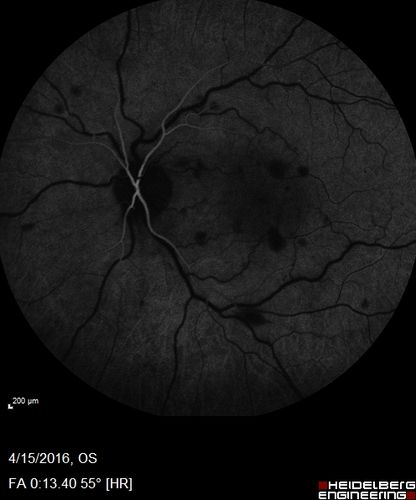

Central retinal artery and vein occlusion - Protein C Deficiency 33 year old male

33 year old male with vision loss for 3 hours.  VA 20/12 right eye, 5/200 left eye.  He has a protein C deficiency.  The left eye recovered vision in about 1 month to 20/16.  FA shows very slow recirculation time.